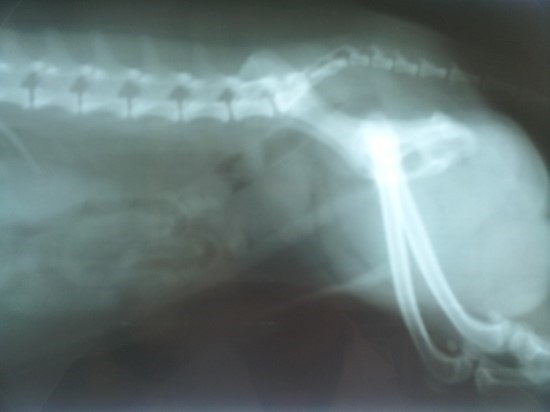

전립선암은 주로 전립선의 바깥쪽 부분인 말초대(Peripheral Zone)에서 발생합니다. 이 때문에 종양이 요도를 압박할 정도로 커지기 전까지는 증상이 나타나지 않는 경우가 많지만, 아래와 같은 비뇨기계 증상 및 전신 증상이 나타나기 시작하면 반드시 정밀 검사가 필요합니다.

- 설명: 전립선이 커지면서 방광에서 소변이 나오는 통로인 요도를 압박하게 됩니다. 이로 인해 소변을 볼 때 소변 줄기가 힘없이 가늘어지고 기운이 없어지며, 이전처럼 시원하게 쭉 뻗지 못하고 옆으로 퍼지거나 똑똑 떨어지는 증상이 나타날 수 있습니다. 이는 전립선 비대증과 가장 유사한 증상입니다.

- 설명: 전립선이 커지면서 방광 출구가 막히거나 방광벽이 자극을 받아 소변이 **자주 마려운 증상(빈뇨)**이 나타납니다. 특히 밤에 잠을 자다가 소변이 마려워 **자주 깨는 증상(야간뇨)**이 두드러지게 나타납니다. 밤에 화장실을 가느라 수면의 질이 크게 떨어지는 것이 특징입니다.

- 설명: 소변을 보고 난 후에도 방광이 완전히 비워지지 않은 것처럼 소변이 남아있는 듯한 찝찝한 느낌이 지속됩니다. 전립선이 요도를 막아 방광이 완전히 수축하지 못하고 소변이 고여있기 때문에 생기는 현상입니다. 이로 인해 다시 화장실을 가야 하는 불편함을 느낍니다.